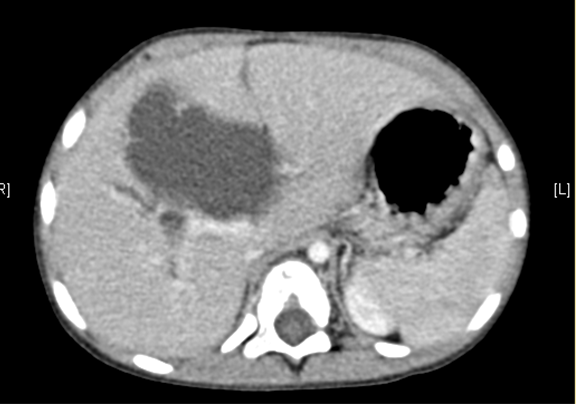

术前CT检查:

动脉期

静脉期

腹部CT 增强:1. 肝内外胆管扩张,考虑胆总管囊肿并胆系扩张可能性大2. 胆囊结石。